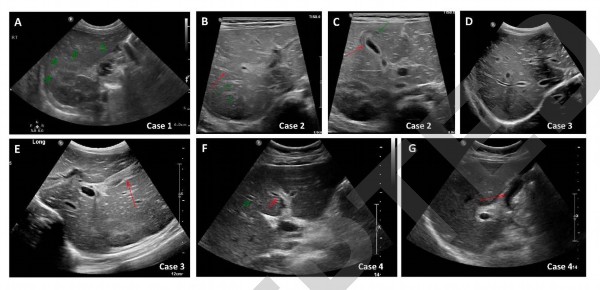

患者1的腹部超声显示门周回声性增加,其他方面不明显(图1A)。随着肝脏合成功能继续恶化,他开始出现脑病,需要肝移植。由于病情进一步恶化,患者1在第32天接受了父亲的活体左侧肝移植手术。患者1的肝脏组织学检查显示,门静脉区域和薄壁组织均有中央周围和全小叶坏死、明显的胆管增生和淋巴细胞浸润。腺病毒、EBV、CMV、HSV和SARS-CoV-2染色阴性(图2A-C)。病人恢复良好,继续在肝移植诊所进行门诊随访。

对患者2的感染性和代谢原因的实验室检查结果显示,他全血中的腺病毒PCR阳性(表1)。SARS-CoV-2的IgG抗体呈阳性(2629AU/ml)。腹部超声显示肝肿大、胆管扩张、门静脉周围水肿和胆囊壁增厚(图1B和1C)。

对患者3维生素K给药后,其INR为1.5。感染性、自身免疫性和代谢性原因的实验室检查结果为阴性(表1)。腹部超声显示轻度肝肿大、胆管突出和胆囊壁水肿(图1D和1E)。入院第4天,患者3接受了肝活检。组织学检查以门静脉和肝窦淤血、胆管增生以及门静脉间隙和小叶中明显的淋巴细胞和嗜酸性粒细胞浸润为特征。

研究者对患者4进行感染性、自身免疫性和代谢性原因的实验室检查,结果为阴性(表1),SARS-CoV-2的IgG抗体呈阳性(376AU/ml)。腹部超声显示胆管扩张和胆囊壁增厚(图1F和1G)。入院13天后的肝活检显示门静脉和肝窦淤血、胆管边缘扩张和增殖,以及门静脉间隙和小叶中明显的淋巴细胞和嗜酸性粒细胞浸润。

对患者5的感染性、自身免疫性和代谢性原因的实验室检查结果为阴性(表1)。腹部超声检查正常。入院当天,患者开始接受全身类固醇治疗。ALT、AST和ALP水平逐渐下降(图3)。目前类固醇治疗已结束,他的肝酶保持正常。

与成人的描述类似,以色列研究的四名患者超声研究显示胆管或胆囊受累。具体而言,发现肝肿大、胆管扩张、门周水肿或胆囊壁水肿和增厚具有显著意义。在成人中,超声检查结果主要适用于肝内胆管局灶性狭窄,伴有腔内淤泥和管型,与SSC的放射学特征相符。